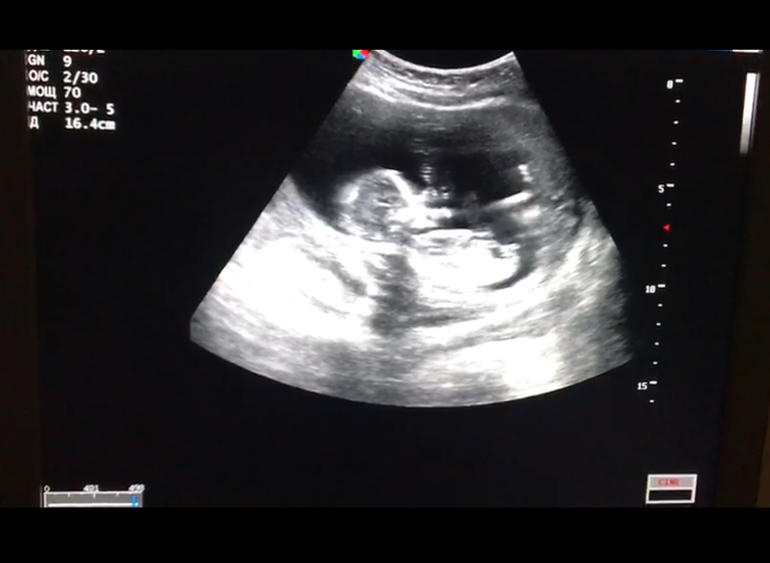

Половой бугорок. Мальчик или девочка?

УЗИ, КТГ, доплерДевочки, кто разбирается, скажите, кто же поселился в домике?) Один врач предположил девочку, второй мальчика)) интрига))) срок 15 недель

Девочка однозначно, бугорок ниже 30 градусов от туловища.По второй фотке отчетливо это видно)